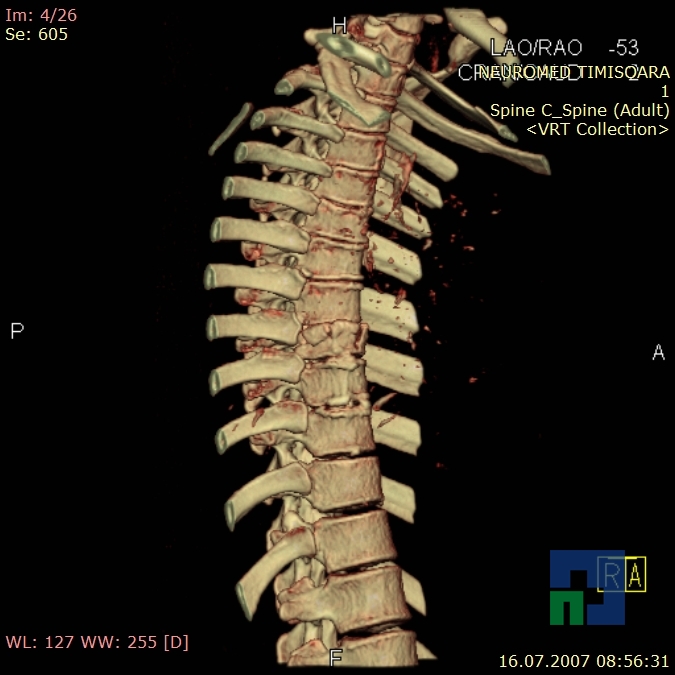

- Diagnosticul fracturilor:

-

- Unice

- Multiple

- Cu înfundare

- Complexe cranio-sinusale

- Complexe cranio-etmoidale

- Complexe cranio-orbitare

- Complexe cranio-faciale